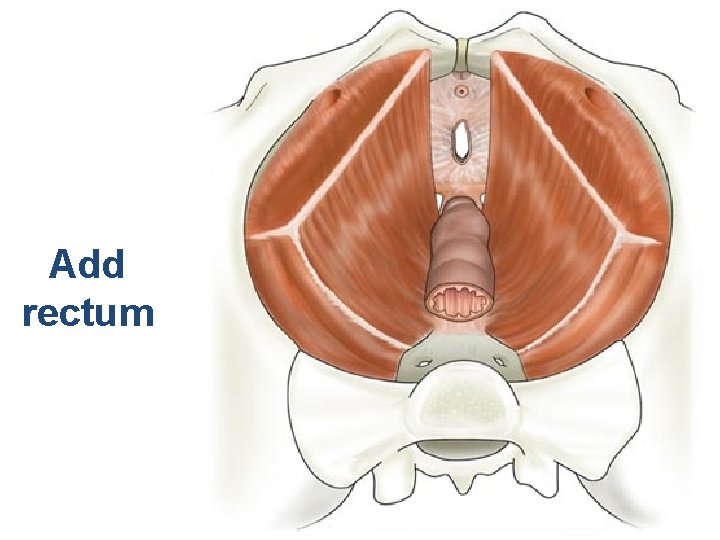

Add rectum